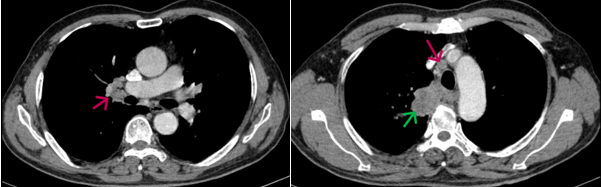

- Chụp cắt lớp vi tính lồng ngực (20/08/2024): Thùy trên phổi phải có khối đặc kích thước ~ 67x39mm, bờ không đều, ngấm thuốc sau tiêm không đồng nhất, dày tổ chức kẽ dạng lưới và kính mờ xung quanh, lân cận có nốt kính mờ đường kính ~5mm, phát triển vào trung thất, đẩy khí quản và thực quản lệch trái, có phần không rõ ranh giới với thành thực quản đoạn ngang mức. Phổi trái giãn phế nang trung tâm tiểu thùy và cạnh vách chủ yếu thùy trên. Trung thất, rốn phổi phải có vài hạch kích thước ~13x17mm, ngấm thuốc không đều sau tiêm.

Hình 1. Hình ảnh khối u thùy trên phổi phải (mũi tên xanh) kích thước 67x39mm, bờ không đều, ngấm thuốc sau tiêm không đồng nhất.

Hình 2. Hình ảnh hạch rốn phổi và hạch trung thất (mũi tên đỏ) kích thước khoảng 13x17mm